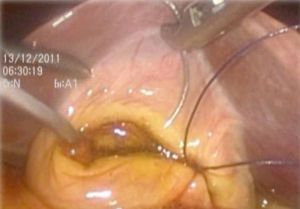

(六)腹腔鏡聯合膽道鏡微創保膽取石術

這種保膽取石方法結合了腹腔鏡和膽道鏡的優點。其同時避免了小切口,做到了儘可能的微創,又使用膽道鏡保證結石的取盡。但由於術中需膽道鏡探查及腹腔鏡下縫合結紮,故操作難度相對較大,準入門檻高。

完全腹腔鏡保膽取石又稱腹腔鏡聯合膽道鏡保膽取石術,其具有腹腔鏡輔助的小切口保膽取石術的優點,同時避免了小切口,做到了儘可能的微創,但由於術中需膽道鏡探查及腹腔鏡下縫合結紮,故操作難度相對較大,準入門檻高,目前僅在腹腔鏡技術較為成熟的醫院開展。